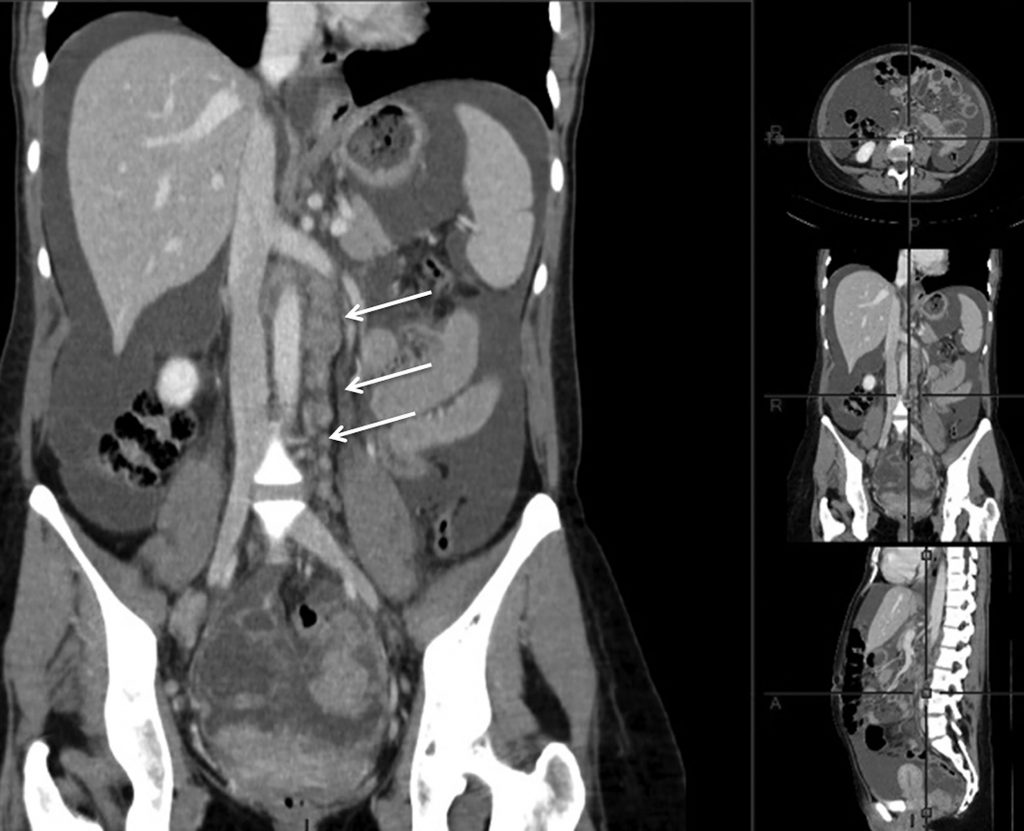

Fig. 23.1 Cystadénocarcinome ovarien.

Scanner abdominopelvien en reconstruction coronale retrouvant une extension lymphatique lombo-aortique (flèches) et une ascite.

Source : CERF, CNEBMN, 2022.